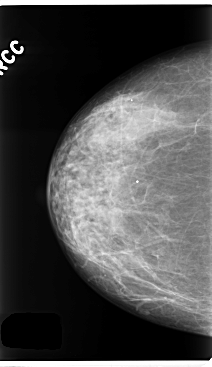

C_0259_1.RIGHT_CC

RIGHT_CC LINES 4760 PIXELS_PER_LINE 2744 BITS_PER_PIXEL 12 RESOLUTION 50 NON_OVERLAY